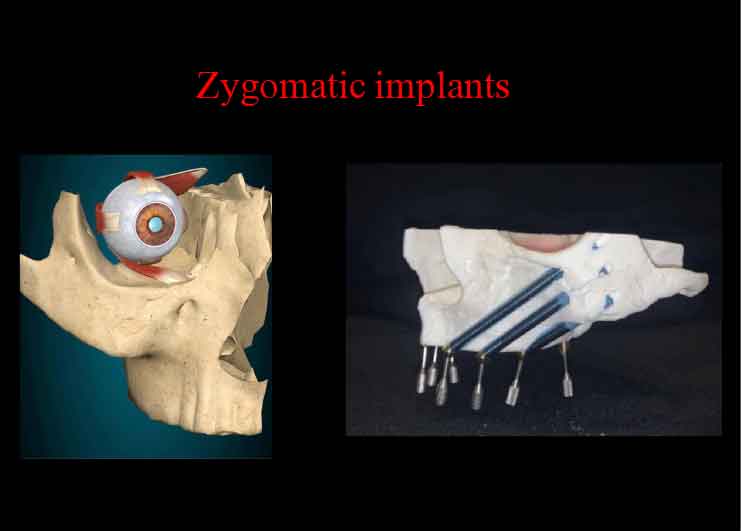

ザイゴマインプラント

上あごの骨が十分にない場合には、強固な頬骨に長めのインプラントを埋め込むことで、しっかりとインプラントを固定することができます。

X-ガイドにより、正確な手術が可能です。

X-ガイドにより、正確な手術が可能です。

プテリゴイド(蝶形骨)インプラント

骨移植など、サイナスリフトを避けた手術を行えます。X-ガイドにより、正確な手術が可能です。